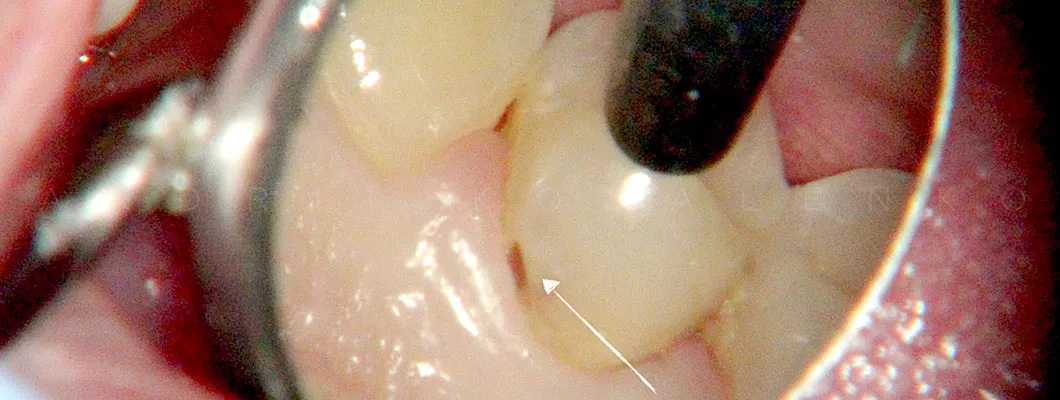

Благодаря эффективному использованию дентального микроскопа, мы можем обнаружить кариозное поражение на самой ранней стадии, которое не доступно невооружённому глазу.

Одним из существенных преимуществ выполнения реставраций с использованием микроскопа в Olanko dental studio (Оланко) г. Бровары — это возможность бережного обращения с зубными тканями.

Работая под увеличением, врач сошлифовывает исключительно поражённые кариесом ткани, а значит, максимально сохраняется объем Вашего зуба.